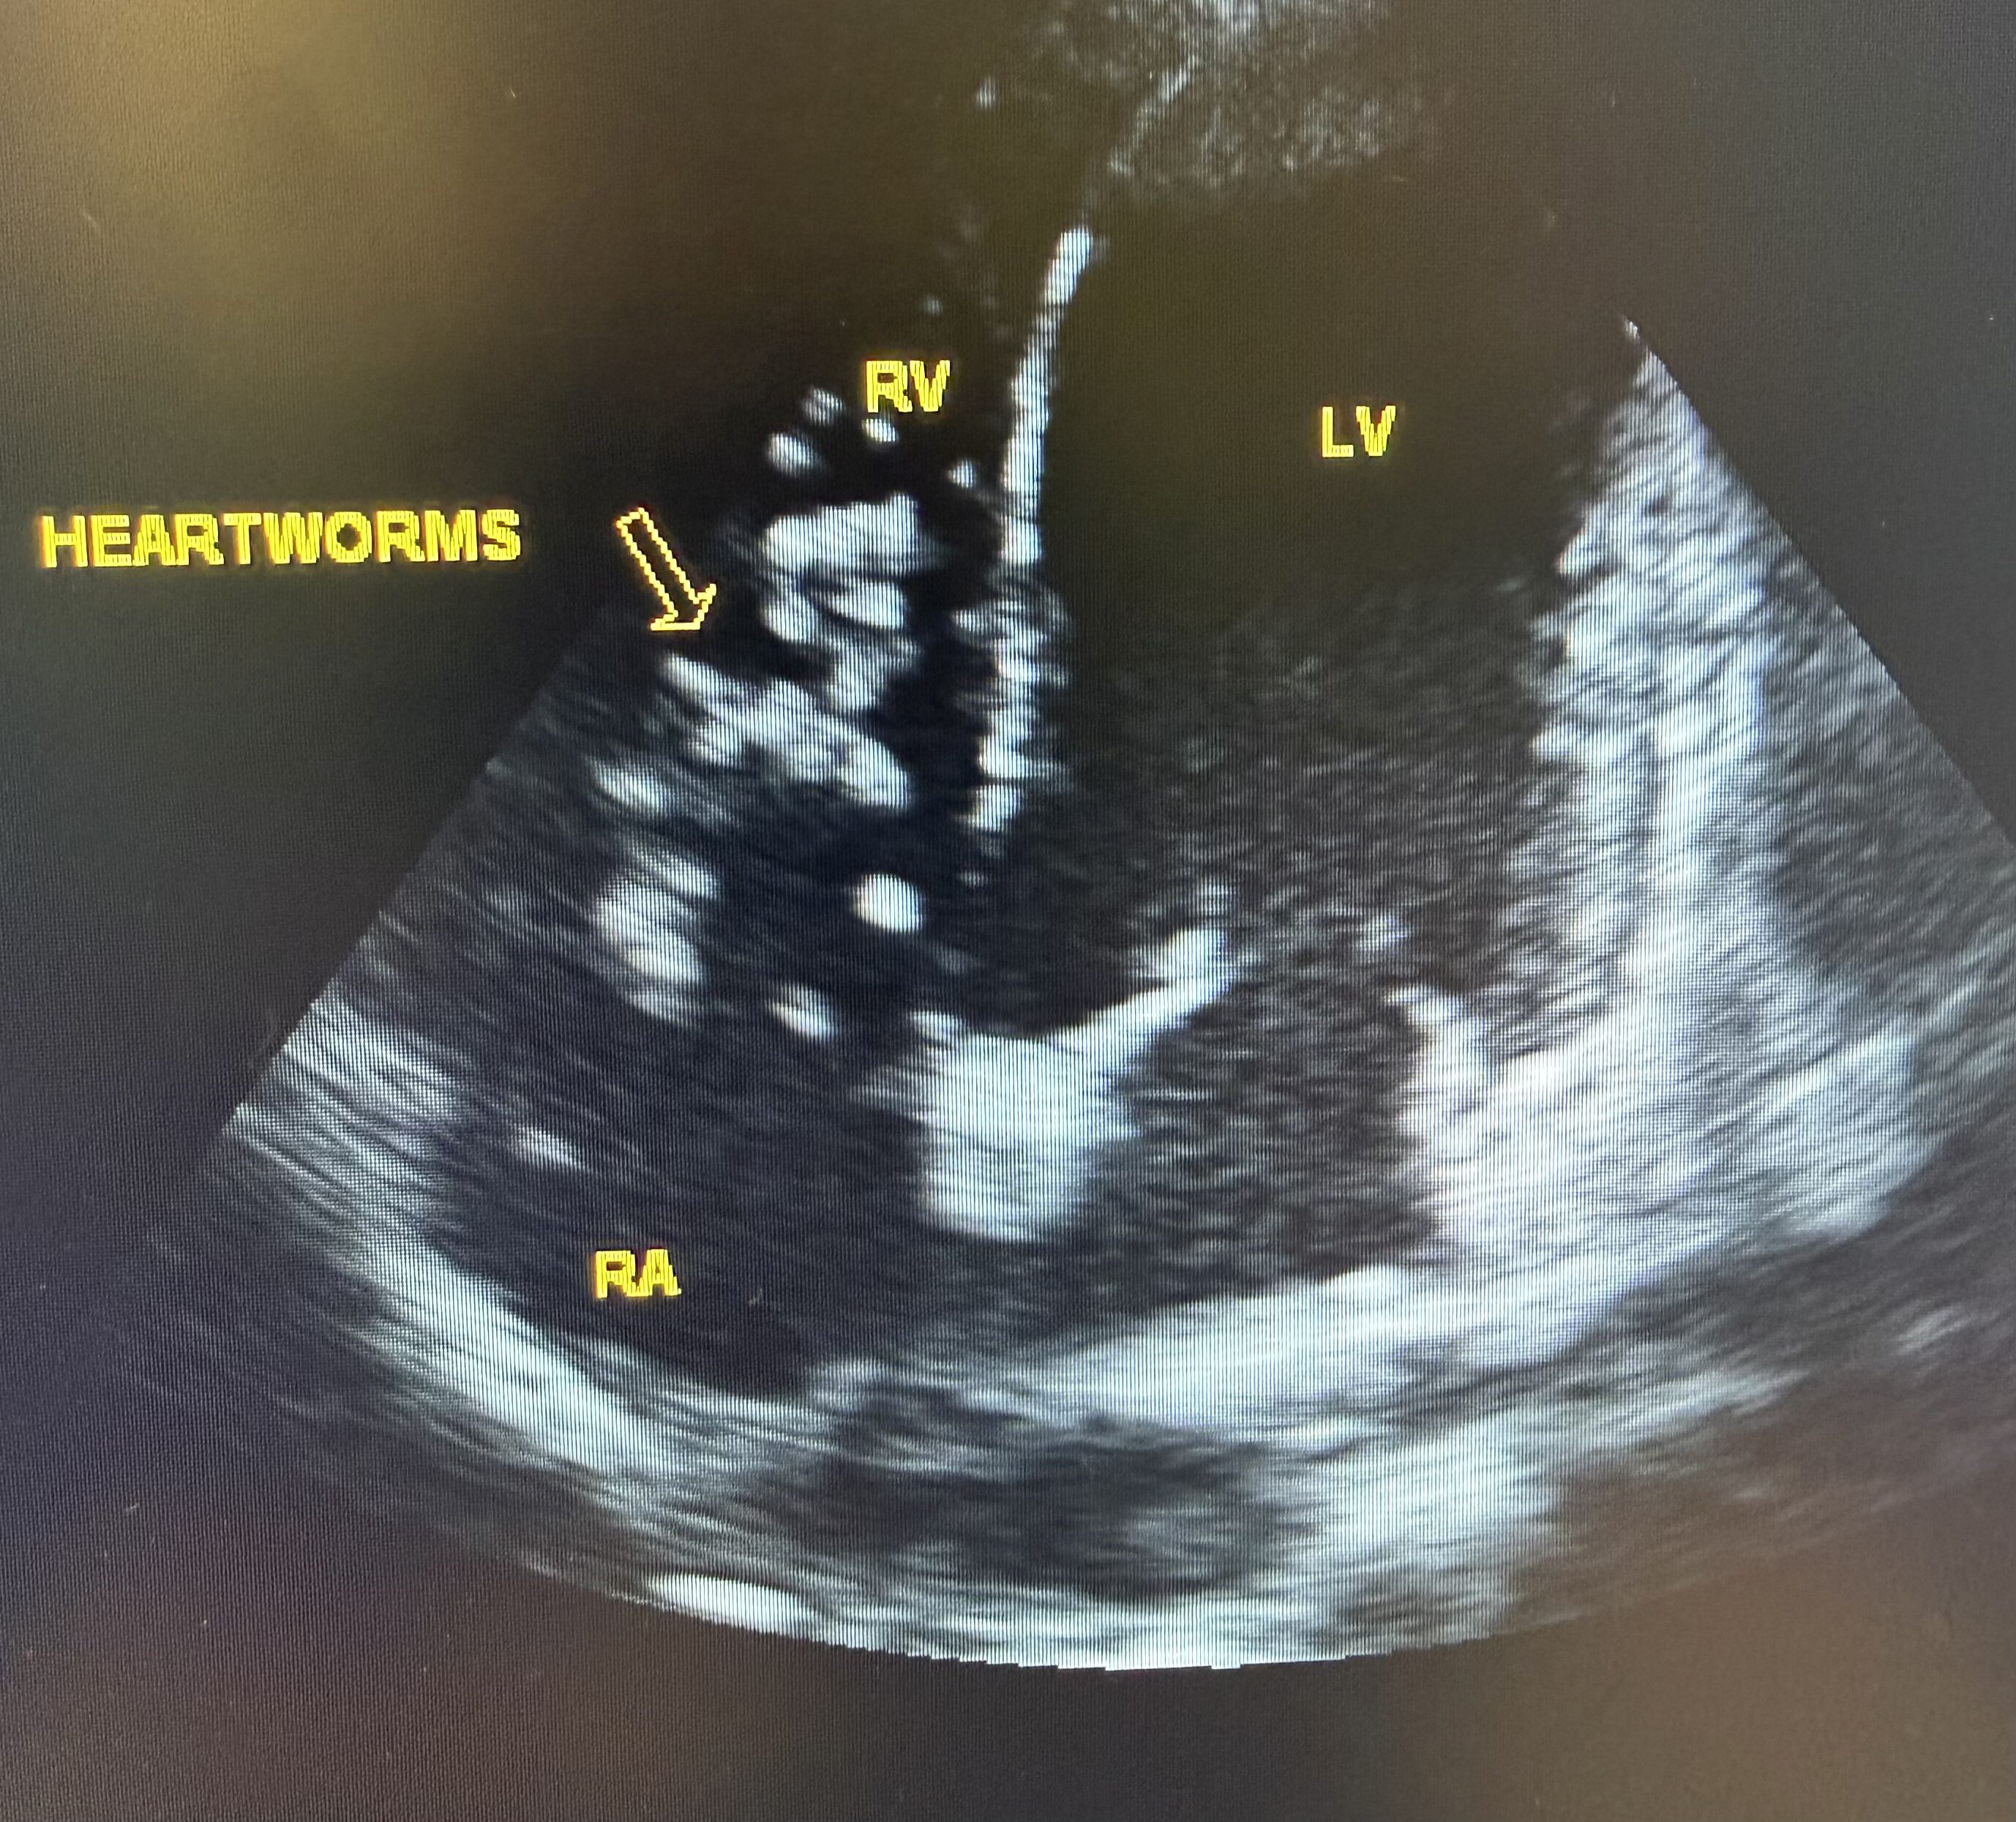

A pet ultrasound is a diagnostic imaging technique that uses sound waves to create real-time images of your pet’s internal organs. This painless procedure allows veterinarians to examine areas such as the heart, liver, kidneys, bladder, and abdominal organs without the need for surgery or invasive tests. It is often used to assess soft tissue structures and monitor ongoing conditions.

- Heart or Liver Disease Monitoring

- Comprehensive Diagnostics: In addition to ultrasounds, Dr. Treadwell performs ultrasound guided aspirates, biopsy, and fluid removal. Dr. Treadwell uses ultrasound in addition to other specialty labs for complete assessment of your pet’s health.